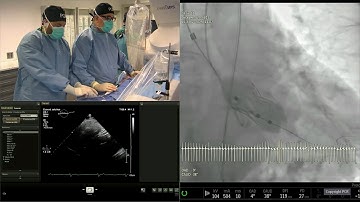

Full core-lab adjudicated results with the new ACURATE neo2 valve - PCR London Valves 2021